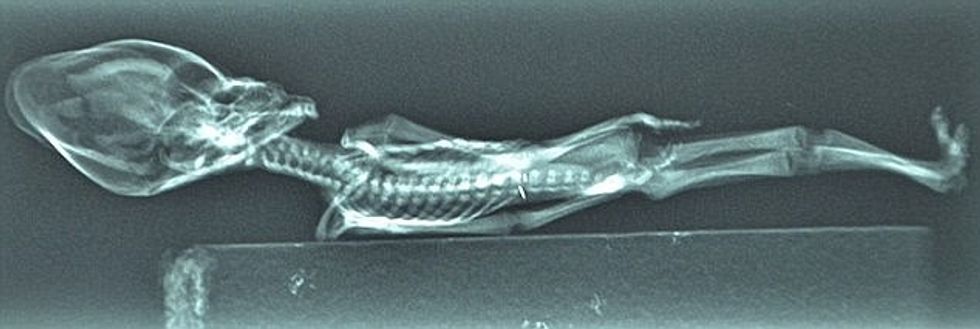

Zbulohet prejardhja e skeletit ‘jashtëtokësor’ me kokë në formë koni (Foto)

Shkencëtarët e kanë zbuluar origjinën e skeletit të gjatë 13 centimetra, që dyshohej se ishte jashtëtokësor.

Trupi me dhjetë brinjë dhe kokë në formë koni, ka marrë nofkën Ata, pasi ishte gjetur në shkretëtirën Atakama të Kilit, gjatë vitit 2003.

Për shkak të dukjes së pazakontë, është menduar se ishte jashtëtokësore, ndërsa u bë pjesë e shumë dokumentarëve, si bazë dhe dëshmi e jetës jashtë planetit tonë.

Fillimisht u besua se ishte fëmijë që ka vdekur gjashtë apo tetëvjeçar, po tani është specifikua që ishte fetus, apo bebe që vdiq menjëherë pas lindjes.